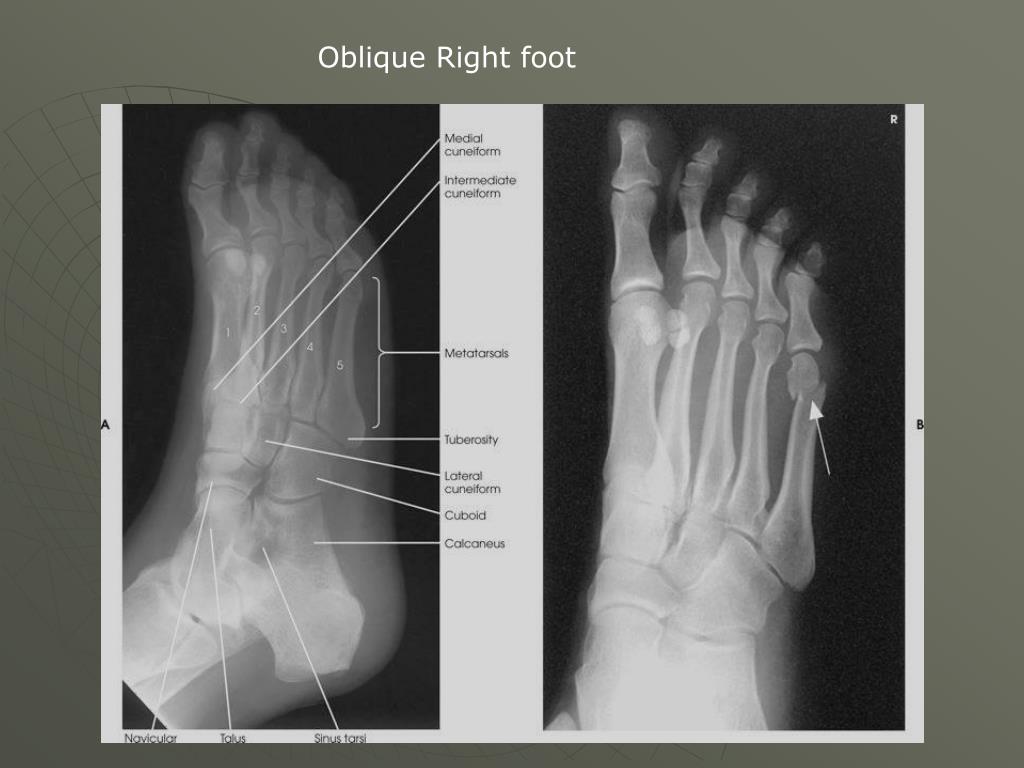

21. Oblique Right foot

15. Tongue depressor Lateral Left 2nd toe

17. AP Right Foot Intermediate Base of the 5th Common area for a foot fracture base of 5th Jones fracture